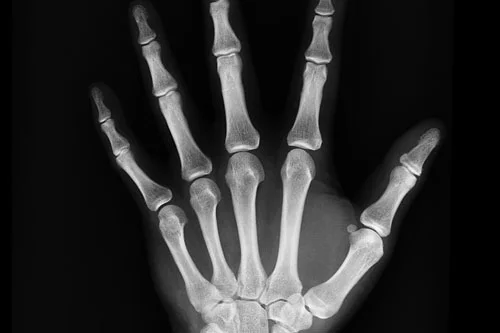

To evaluate the density and subsequently the strength of bones, a DEXA (dual energy X-ray absorptiometry) scan emits very low doses of X-rays. DEXA or bone densitometry are some of the alternate names for it.

The loss of bone density can be identified by DEXA, a quick and precise technique that is more sensitive than standard X-rays in considering bone density. Various bone disorders and medications can contribute to the loss of bone density. A DEXA scan is also useful in assessing injuries and lesions, as well as the success of management.